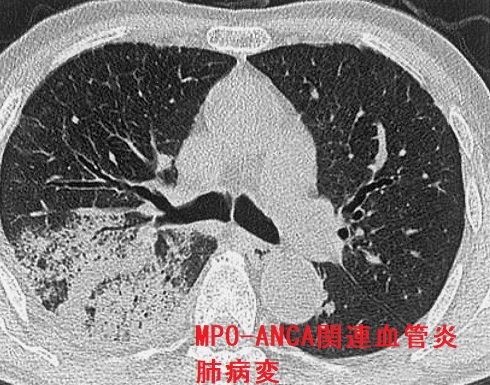

- 肺腎症候群(肺胞出血も)、間質性肺炎

- 肺に病変が及ぶと、①肺胞出血と腎炎の肺腎症候群[J Clin Rheumatol. 2009 Oct;15(7):341-4.]、②間質性肺炎の合併(稀)[Intern Med. 2003 Oct;42(10):1026-30.]

PTU(プロパジール、チウラジール)服用中に感冒症状を認め、通常の風邪治療では治らない場合、

- 肺CTを撮影

- 肺胞出血を疑う

- 肺腎症候群としてANCA関連腎炎を伴う場合

- 肺胞出血単独の場合

の2通りがあります。